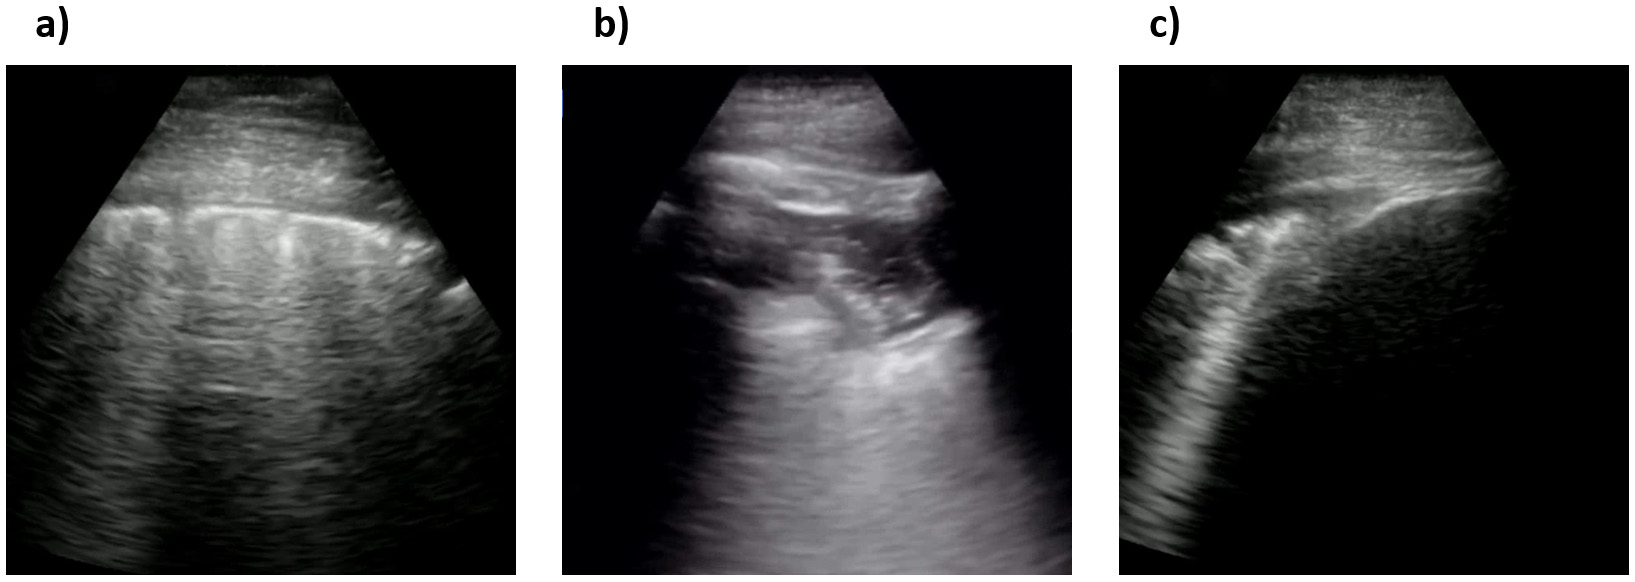

Fig. 2 shows sample ultrasound frames captured from the ultrasound video recordings in the COVIDx-US dataset. The examples are processed by the COVIDx-US scripts. These few examples illustrate the diversity of ultrasound imaging data in the dataset. The choice of the nine different data sources and the heterogeneity in the structure and format of their hosted videos resulted in a highly diverse set of videos and images in the COVIDx-US dataset that is key to the generalizability of the AI-driven solutions/models that are built/trained on the COVIDx-US dataset. Additionally, this non-homogeneous set of data points could provide researchers with more flexibility in their research projects via filtering in/out data points based on their research objectives. We will continuously grow the dataset by adding more data points and/or data sources.

Fig. 2.Sample ultrasound frames captured from the curated ultrasound video recordings in the COVIDx-US dataset. (a), (b), and (c) COVID-19 positive cases, (d) and (e) non-COVID-19 infection cases, (f) a normal control case. The dataset comprises 173 ultrasound videos, collected and curated systematically from nine different data sources, and 21,570 carefully curated ultrasound images in the current version.